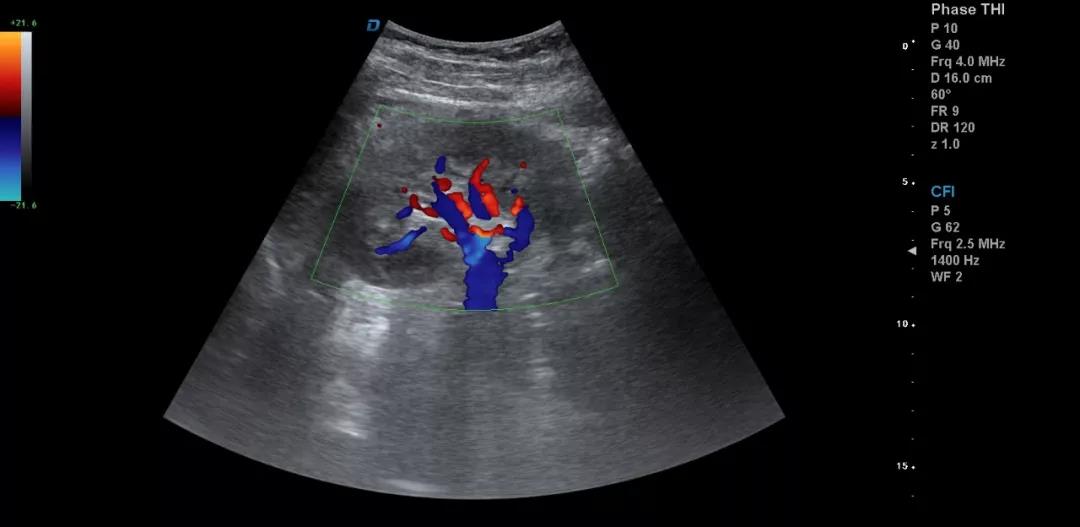

一個正確的診斷往往是醫學理論、臨床經驗和正確思維方法三者有機結合的結果。醫用B超機作為一種常見的檢查儀器,對某些疾病的診斷具有明顯優勢,已成為一種便捷、無創、有效的檢查手段。因此,超聲診斷的目標就是減少漏診、誤診,或為最終診斷提供更多更有價值的信息。